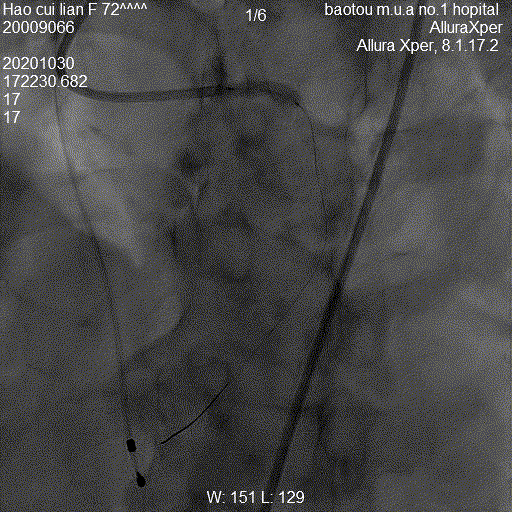

图:手术流程图